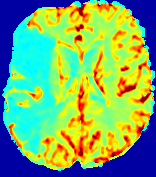

Slice #1Slice #2Slice #3Slice #4Slice #5Slice #6Dgtsuperscript𝐷gtD^{\text{gt}}Refer to captionRefer to captionRefer to captionRefer to captionRefer to captionRefer to caption(a)Refer to captionRefer to captionRefer to captionRefer to captionRefer to captionRefer to caption(b)Refer to captionRefer to captionRefer to captionRefer to captionRefer to captionRefer to caption(c)Refer to captionRefer to captionRefer to captionRefer to captionRefer to captionRefer to caption(d)Refer to captionRefer to captionRefer to captionRefer to captionRefer to captionRefer to caption(e)Refer to captionRefer to captionRefer to captionRefer to captionRefer to captionRefer to caption(f)Refer to captionRefer to captionRefer to captionRefer to captionRefer to captionRefer to captionRefer to caption000.060.060.060.120.120.120.180.180.180.240.240.240.300.300.30(mm2/s)𝑚superscript𝑚2𝑠(mm^{2}/s)

Figure 13: PIANO effectiveness and robustness testing: diffusion imaging via diffusion. Top row shows Dgtsuperscript𝐷gtD^{\text{gt}} used for simulating the ground truth pure diffusion. (a)-(f) refer to the results for D𝐷D estimated from the ground truth pure diffusion image time-series where Rician noise at levels 0%, 2%, 4%, 6%, 8%, 10% was added respectively.

Similarly, starting from the same initial condition C0superscript𝐶0C^{0} as in the ‘Advection Imaging’ experiment for each patient, we simulate concentration time-series {Cti(Ω)|i=0, 1,, 40}conditional-setsuperscript𝐶subscript𝑡𝑖Ω𝑖0140\{C^{t_{i}}\in\mathbb{R}(\Omega)|i=0,\,1,\,\ldots,\,40\} via a diffusion PDE, where we define the ground truth diffusivity D:=Dgtassign𝐷superscript𝐷gtD:=D^{\text{gt}} via the ADC map of the ISLES 2017 training set (ADC values are scaled by 0.000010.000010.00001 to ensure numerical stability):

Note this is likely not a spatially representative ground-truth for perfusion imaging, as it measures different effects from diffusion imaging. However, we still use it as a quasi-realistic pattern of diffusivity in the brain. We also added 2%, 4%, 6%, 8%, 10% levels of Rician noise to obtain simulations of ‘Diffusion Imaging’. The estimated Destsuperscript𝐷estD^{\text{est}} given concentrations of all noise levels for one patient are shown in Fig. 13, PIANO estimation results for all patients are summarized in Fig. 11 (b). Again, PIANO demonstrates its capability to recover the underlying diffusion field. In Fig. 13, when the noise level is increasing, some noisy patterns indeed appear in the associated Destsuperscript𝐷estD^{\text{est}}. Note that the ground truth diffusivity applied in this simulation experiment is about ten times larger than the diffusivity estimated in reality (Fig. 3, Fig. 4).